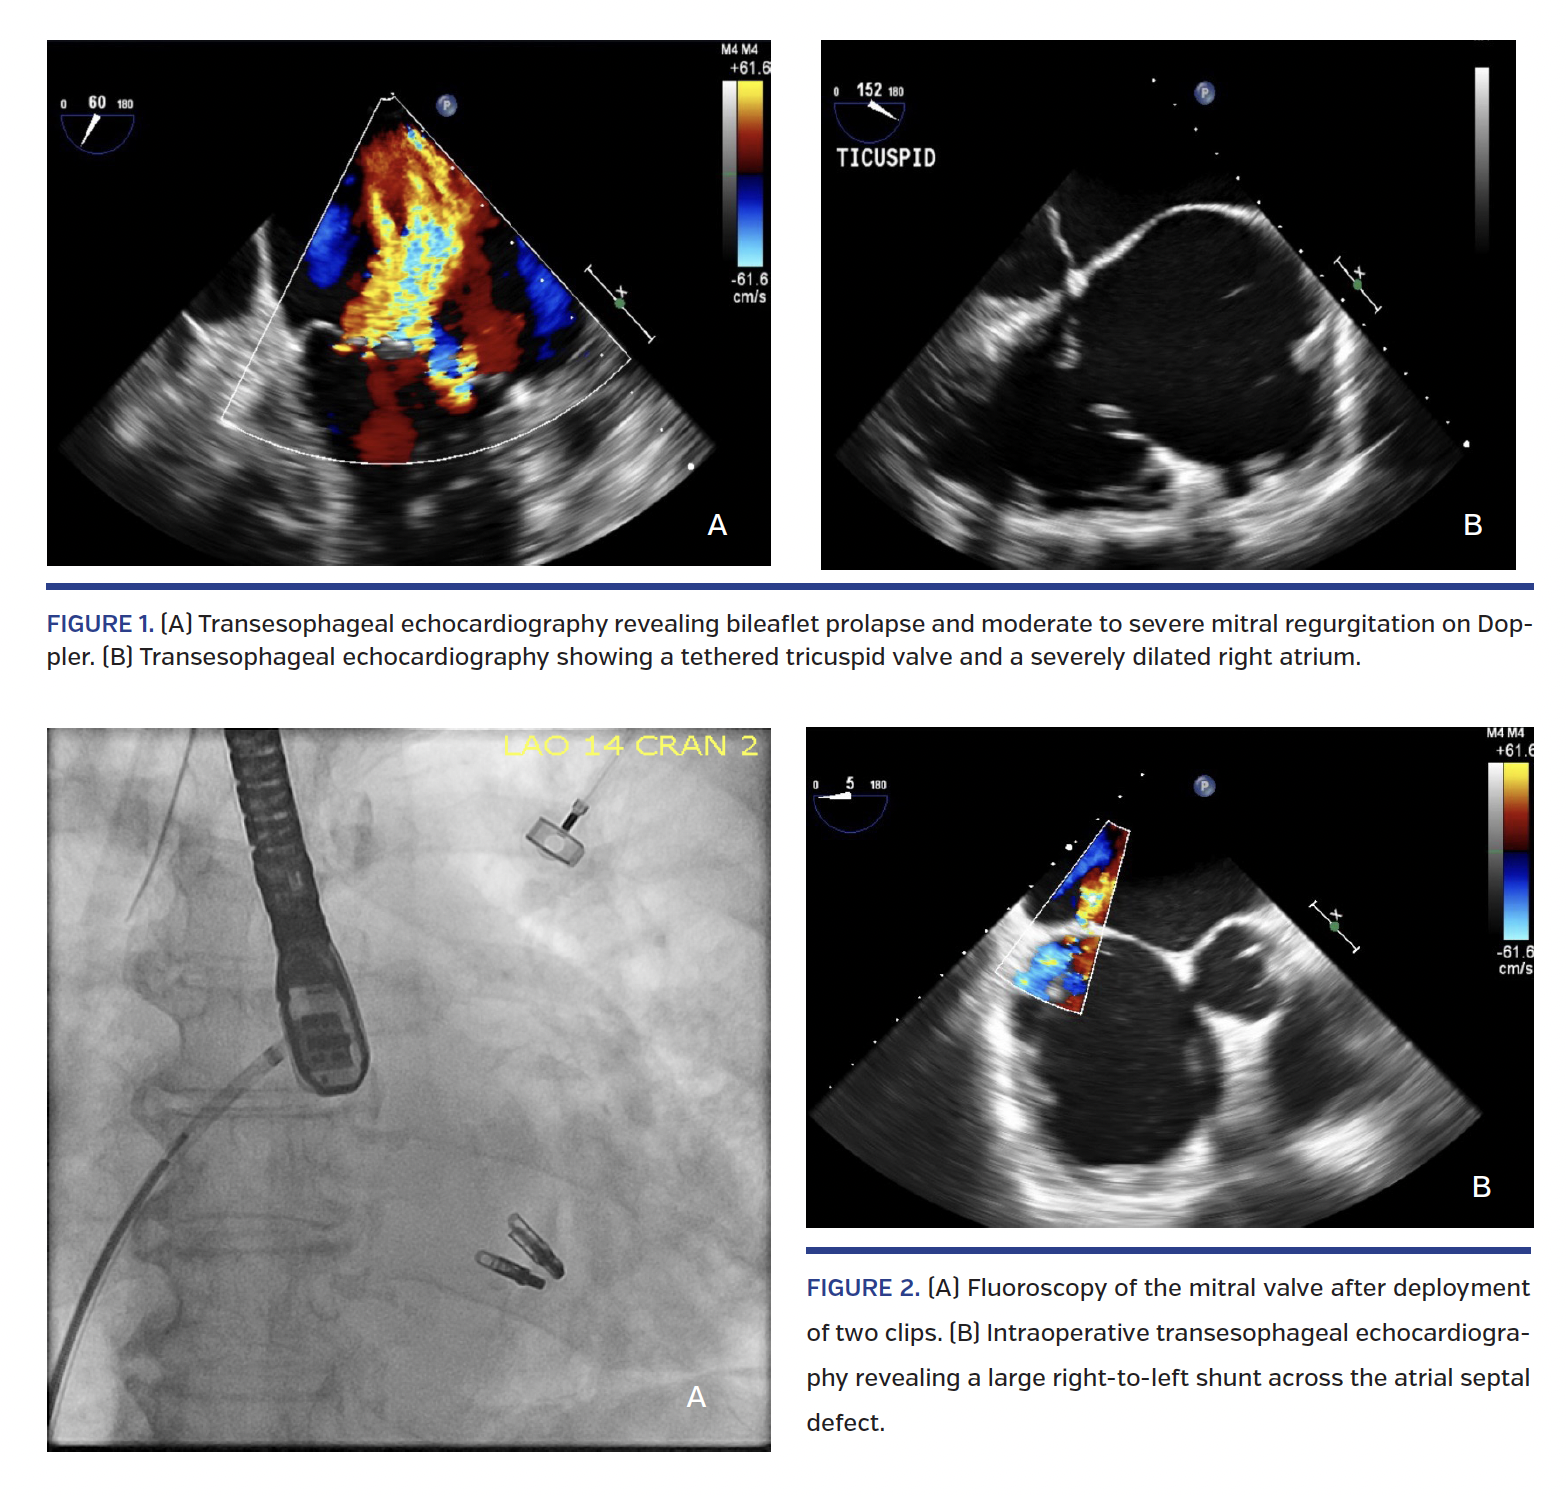

An 86-year-old female with history of coronary artery disease and a previously placed right coronary artery stent, atrial fibrillation on apixaban, normal left and right ventricular function with moderate-to-severe primary mitral regurgitation, and recurrent hospitalizations for heart failure was deemed a high-risk surgical candidate and underwent percutaneous repair of the mitral valve. Preoperative transesophageal echocardiography (TEE) revealed thickened mitral valve leaflets with normal opening and bileaflet prolapse (Figure 1A). Echocardiography also revealed severe tricuspid regurgitation with tethering of the leaflets due to tricuspid annular dilation and a severely dilated right atrium (Figure 1B). Intraoperatively, venous access was obtained and a 22 Fr sheath was advanced into the left atrium after TEE-guided transseptal puncture. Left atrial pressure was measured at 15 mm Hg (v-waves to 20 mm Hg) and right atrial pressure was 18 mm Hg (v-waves to 24 mm Hg). Using TEE and fluoroscopic guidance, two clips were placed after confirmation of satisfactory position; TEE showed a reduction of the mitral regurgitation to mild with no transmitral gradient (Figure 2A).

Once the 22 Fr guiding sheath was removed, a significant right-to-left shunt developed (Figure 2B), with the patient’s oxygen saturation acutely dropping from 100% to 89% on high-flow oxygen. Therefore, the atrial septal defect was closed with an 8 mm Amplatzer atrial septal occluder device (St. Jude Medical) with oxygen saturation recovering to 98%. Postoperatively, the patient had an uncomplicated course and was discharged in stable condition.